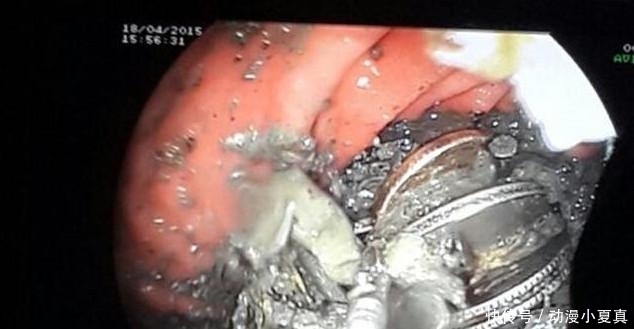

但是在医生的简单的处理下,该男子的情况没有好转而更加疼痛,家人十分焦急。医生很诧异,研究后决定给男子做X检查以及胃镜检查,检查后的结果让在场所有的医护人员感到吃惊,男子胃里的东西让临床多年的医生感到害怕。

男子胃里到底是什么呢?最有医生给出了结果。男子的胃里居然是金属物品,并且里边的金属物品还杂乱无章,粗略的估算下,有一百多枚钱币、几十根银还有些许螺丝、螺栓,让医生感到吃惊的还有废弃电池。医生非常诧异,难道男子把自己当成了机器人?医生把检查的结果告知了男子家人,并且医生告诉男子家人,必须要马上做手术,要不然该男子会因此而丧命。